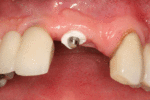

From these theoretical risks, derive the real world complications. Long-term failures are due to either loss of bone around the tooth and/or gingiva due to peri-implantitis or a mechanical failure of the implant. Because there is no dental enamel on an implant, it does not fail due to cavities like natural teeth. While large-scale, long-term studies are scarce, several systematic reviews estimate the long-term (five to ten years) survival of dental implants at 93–98 percent depending on their clinical use.[1][2][3] During initial development of implant retained teeth, all crowns were attached to the teeth with screws, but more recent advancements have allowed placement of crowns on the abutments with dental cement (akin to placing a crown on a tooth). This has created the potential for cement, that escapes from under the crown during cementation to get caught in the gingiva and create a peri-implantitis (see picture below). While the complication can occur, there does not appear to be any additional peri-implantitis in cement-retained crowns compared to screw-retained crowns overall.[40] In compound implants (two stage implants), between the actual implant and the superstructure (abutment) are gaps and cavities into which bacteria can penetrate from the oral cavity. Later these bacteria will return into the adjacent tissue and can cause periimplantitis. As prophylaxis these implant interior spaces should be sealed.[41]